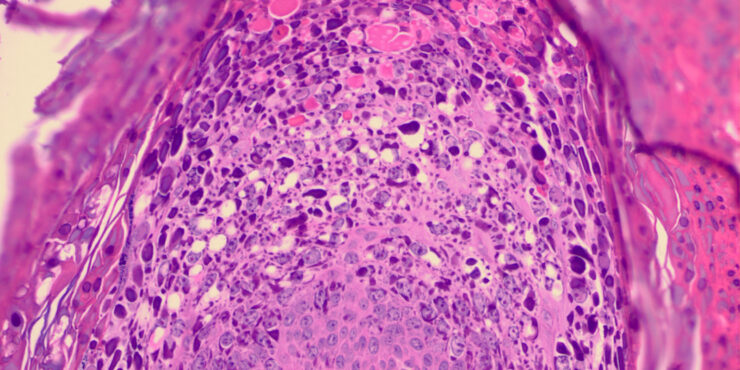

Vaccinia =الوقس =جدري البقر